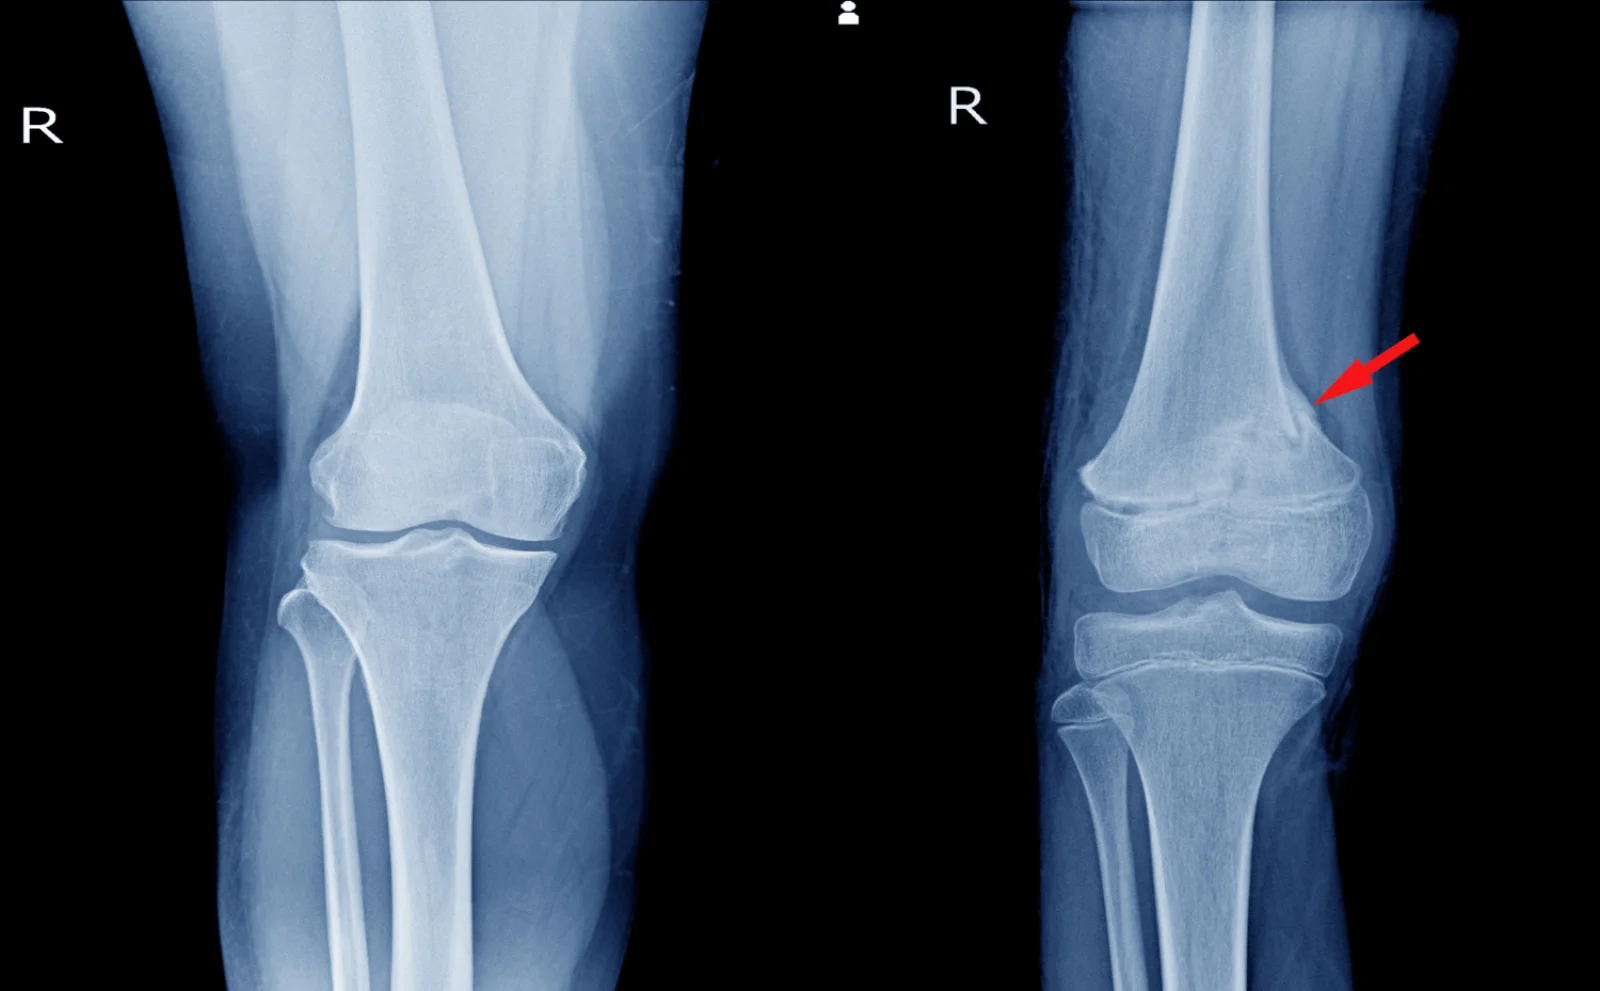

Intramedullary nailing is a surgical procedure used to treat fractures of long bones such as the femur or tibia by inserting a metal rod inside the bone canal.

Intramedullary nailing is an orthopedic surgical technique used to stabilize fractures of long bones. During the procedure, a metal rod called an intramedullary nail is inserted into the hollow center of the bone to keep the fractured pieces aligned while healing occurs.